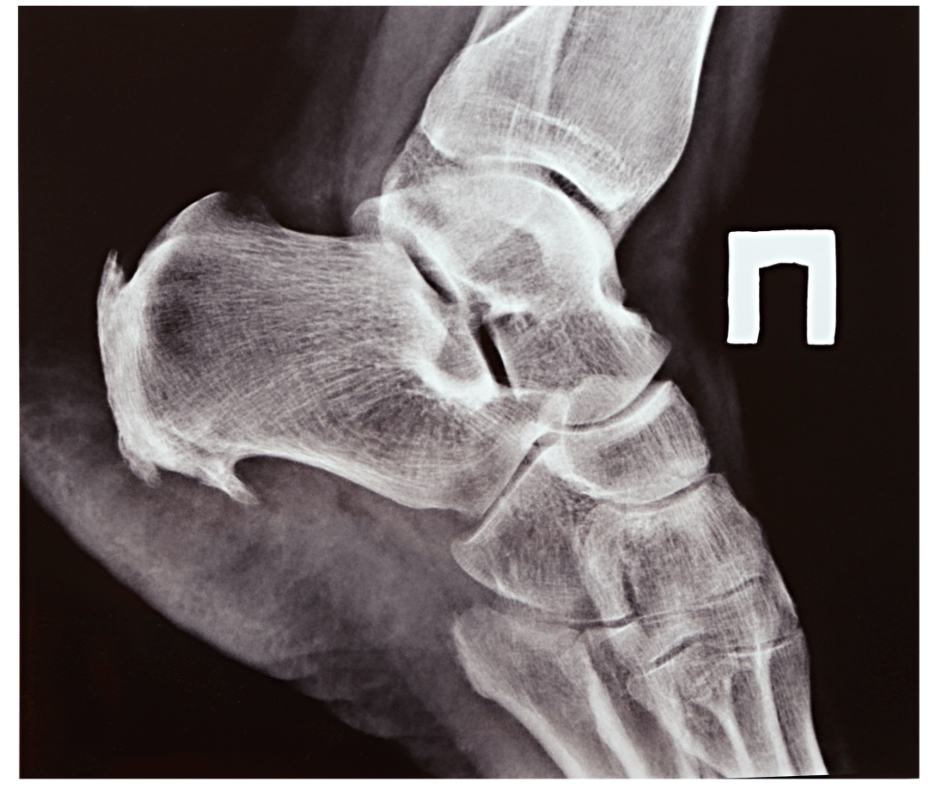

La maladie de Haglund, également connue sous le nom de syndrome de Haglund, est une affection du pied qui se caractérise par une inflammation de l'os du talon et des tissus environnants. Cette condition est également appelée "exostose postérieure du calcanéum".

Comment diagnostiquer la maladie de haglund, quelle évolution du pied ?

Le diagnostic est généralement basé sur un examen physique et des tests d'imagerie. L'évolution dépend de la gravité de la condition et de la manière dont elle est traitée.